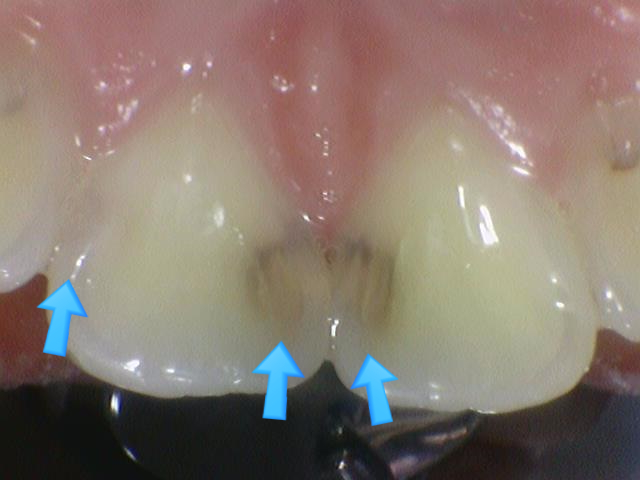

앞니사이 충치치료 레진치료

충치 3군데

입천장쪽에서 보면 충치 세 군데가 보입니다.

화살표 세 개중 맨 왼쪽 화살표가 가리키는 쪽은 충치가 명확하게 보이지 않지만

아주좋은 [!] 전문가의 눈으로 보면 충치가 비쳐보인다는 것을 알 수 있습니다.(대칭되는 반대쪽과 비교)

왼쪽 화살표 충치는 엑스레이로 다시 한번 명확하게 확인 하였습니다.